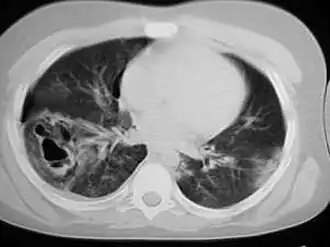

Description de cette image, également commentée ci-après

Une tomodensitométrie thoracique révélant des contusions pulmonaires, un pneumothorax et des pseudokystes